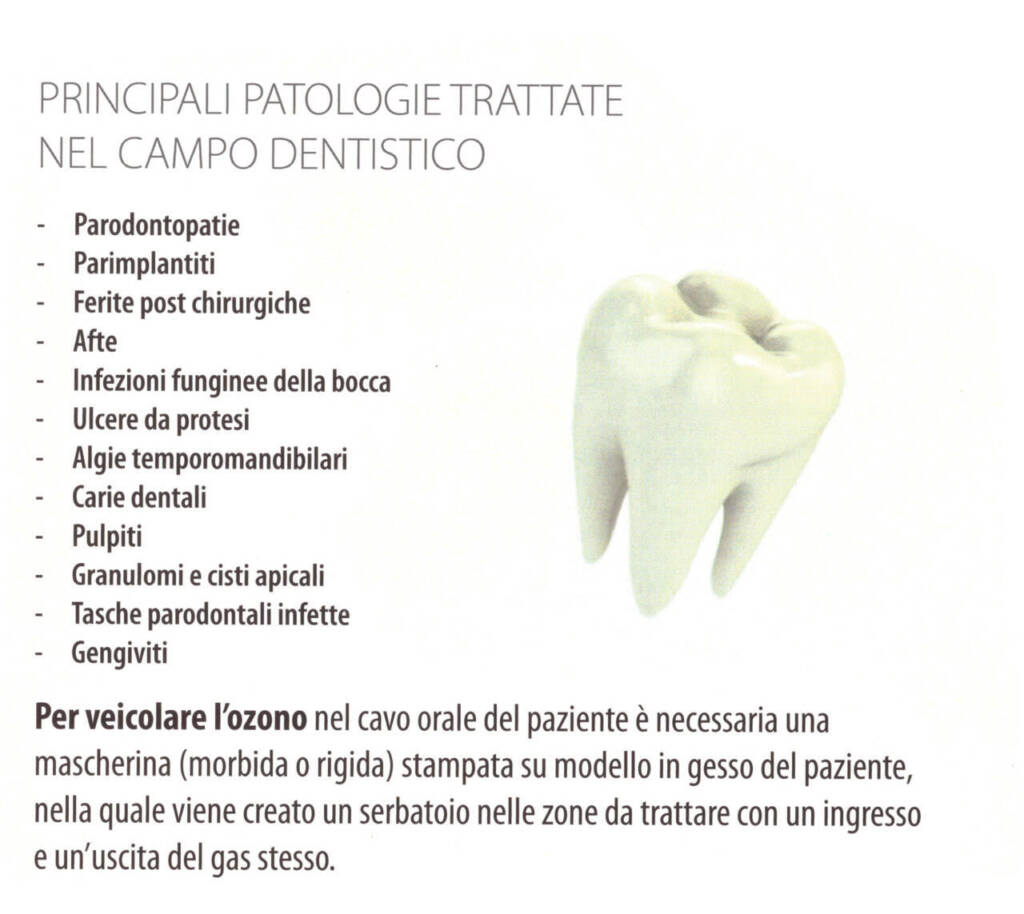

Nell’Odontoiatria: efficace nel trattamento della carie, nella disinfezione post chirurgia impiantare, nell’osteonecrosi, gengiviti, stomatiti e dolori masticatori.